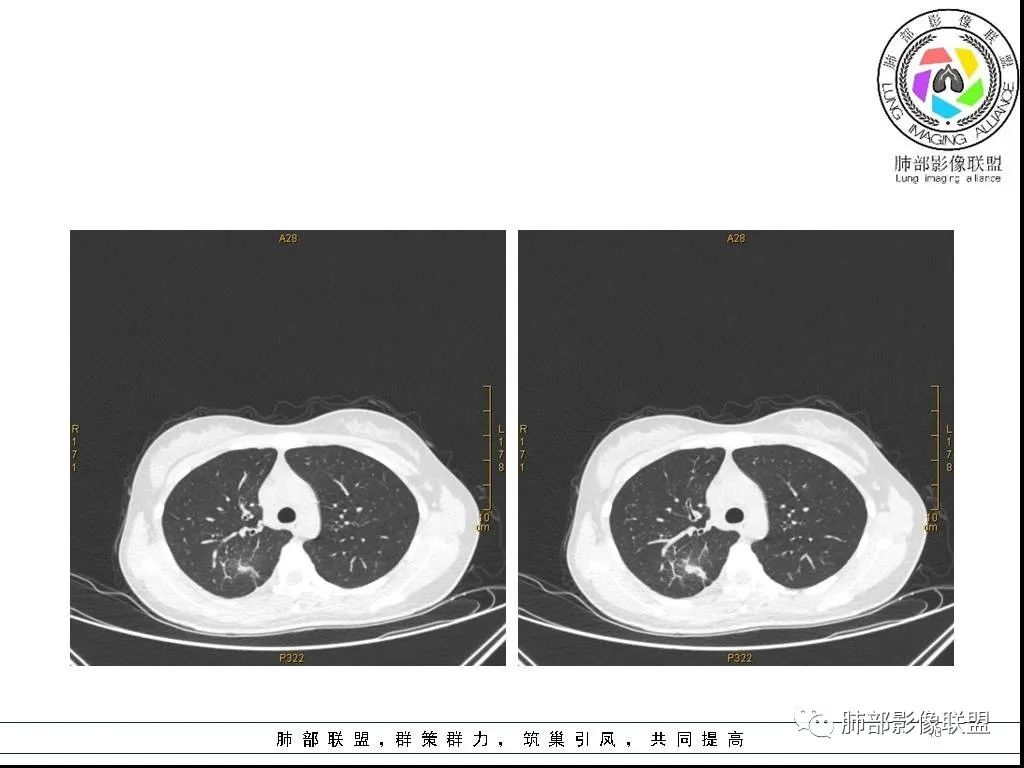

右肺炎症性病变1例CT影像讨论

年轻女性,病程长,咳嗽少痰4个月,辅检未见特殊,CT:右肺团块影,跨叶,主体在下叶背段,外大内小,边缘以膨隆为主,部分平直内收,深分叶,周围有模糊晕,可疑卫星灶,胸膜增厚,糊墙,支气管近端部分进入,粘液栓,有坏死空腔,内壁光整,部分血管侵蚀,强化不均,延迟,明显;同侧R10、7、R4淋巴结肿大,考虑肉芽肿炎,结核,需要与肿瘤鉴别:16岁,女性,诊断肿瘤需要勇气,跨叶多见于炎性,需要进一步活检。

右肺上叶后段及下叶背段条带状影,病灶边缘整体以收缩平直为主,部分膨隆,延支气管由外朝内蔓延,不受叶段限制,外围大,近肺门区小,其周散在结节状卫星灶及部分GGO,中度不均质强化,血管穿行受侵,邻近胸膜反应性增厚。青少年慢性病程,咳嗽咳痰,总体倾向炎性肉芽肿,结核可能性大。

青少年女性,咳嗽咳痰4个月,血沉快,ppd阴性。右肺上叶后段及下叶背段可见一长条块影,边缘平直,有收缩及凹陷,局部有膨隆,长轴与支气管平行,近段支气管似有粘液栓阻塞,血管进入后有破坏,周围有磨玻璃影及少许卫星灶,中度不均匀强化,局部胸膜增厚,少量积液,考虑炎性肉芽肿,肺结核可能性大,鉴别op,淋巴瘤,肺癌。

青少年女性,阵发性咳嗽4月,慢性病程,血沉快,ppd阴性。右肺上叶-下叶跨叶生长的不规则实变影,长轴与胸膜平行,边缘平直征,部分边缘模糊,中度强化,临近胸膜增厚黏连,考虑炎性肉芽肿性病变,结核可能,鉴别诊断:炎性肌纤维母细胞瘤、隐球菌等。 医学百科网 | YxBaike.Com

病灶收缩、跨叶,应当想到存在有畸形的、发育异常的叶裂,一个副叶的病变。这个病灶明显在后段下方,斜裂的上方,靠近肺门侧的叶裂显示不是很清楚,这个应该是副叶来的,不是后段的分支。

病灶内部存在管状分布液性低密度区,这与复查显示的柱状管样气腔对应吻合,支持先天性支气管扩张的存在,仅仅是影像未能显示出入口。

炎性病变的诊断当无异议。患者疗效颇佳,除抗生素覆盖合理外,推测与支气管引流改善密切相关! 医学百科网 | YxBaike.Com